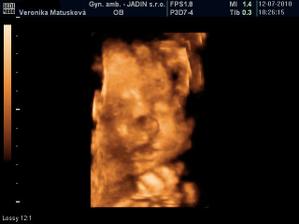

Adamko - 3D/4D

No tot vidno, že je náš syn, sa hanbil a hanbil až sa ukazovať nechcel....ale niekedy sa to podarilo, aj ked to nie je nejaká sláva. Pán doktor nám potvrdil chlapčeka, tak sme radi, vajká ukazoval ako len vedel len toho pipíka stále schovával. Ale je to za nami, pán doktor nás pekne popísal čo je kde, poodmeral nás a povedal, že je všetko v poriadku.